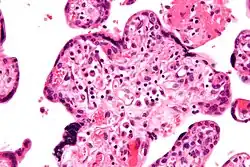

Микрофотография виллита неизвестной этиологии, патологии плаценты, связанной с задержкой роста плода. Окраска гематоксилином и эозином.

Существуют различные факторы риска, которые могут способствовать задержке роста плода. Они включают социально-бытовые факторы (например, молодой или пожилой возраст матери, злоупотребление психоактивными веществами, вредные или тяжёлые условия труда, эмоциональное перенапряжение, недостаточный вес матери), тератогенные факторы (воздействие циклофосфамида, вальпроевой кислоты, антитромбических препаратов)[3], соматические факторы (хронические инфекции, заболевания вне половой сферы), акушерско-гинекологические факторы (проблемы с предыдущими беременностями и родами, гинекологические заболевания, аномалии матки) и факторы, связанные с текущей беременностью (токсикозы, гестоз, многоплодная беременность, угроза прерывания беременности)[2]. Также плодовые факторы (конституциональные особенности, наследственные синдромы, аномалии развития плода, внутриутробные инфекции) могут играть роль в задержке роста плода[2].